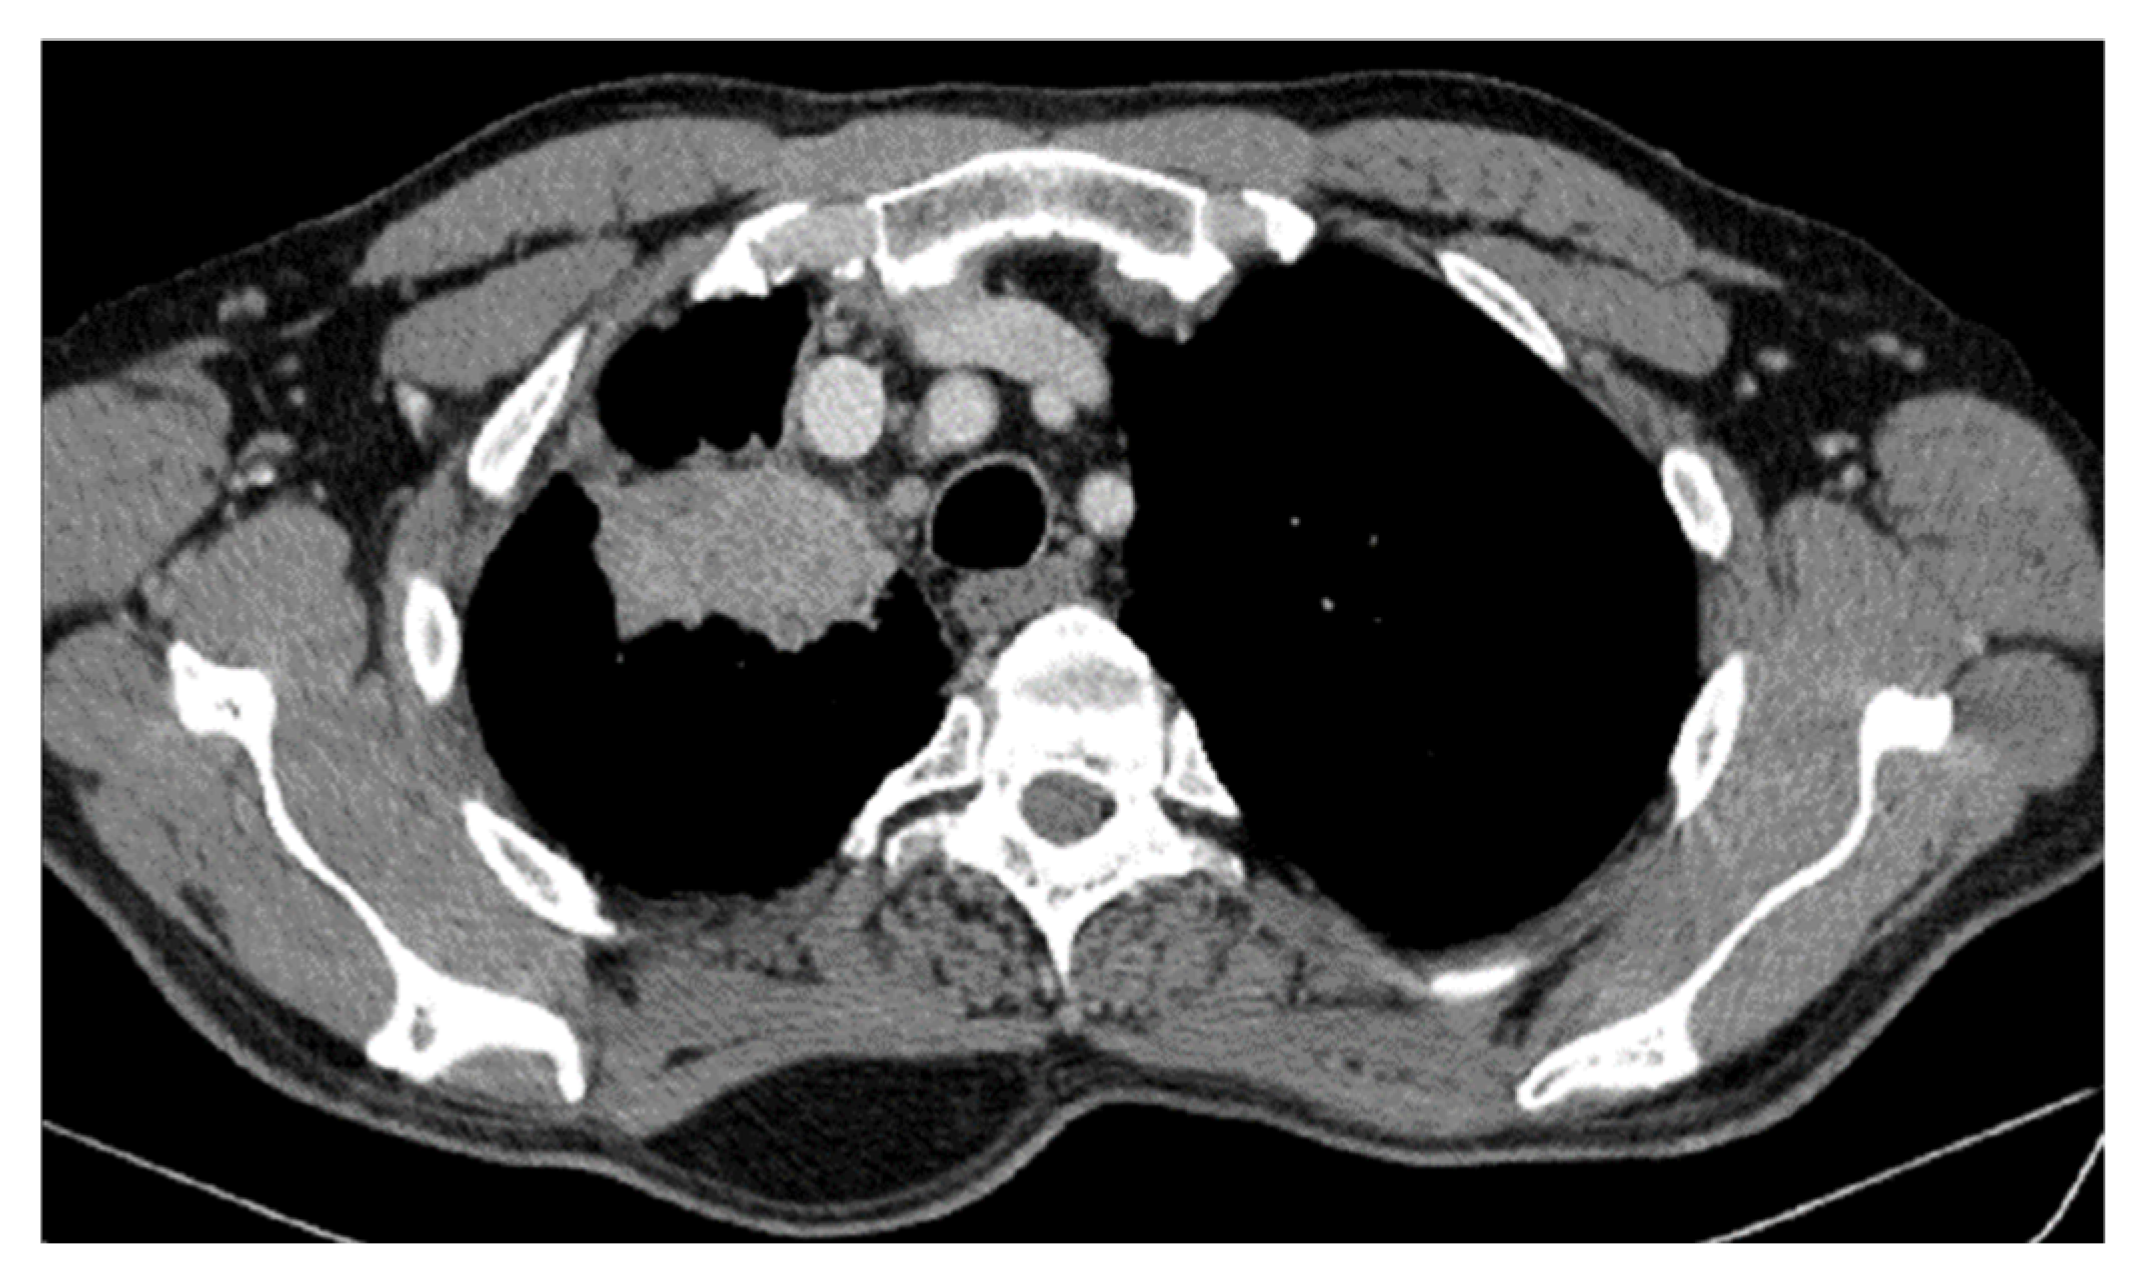

2. Case Presentation

2.2. Monitoring 2022: Oncological Commission 1910/16.08.2022

2.3. Oncological Committee 07/25/2023 Recommended

- Consider rescue re-irradiation (SBRT), taking into account the current primary tumor dimensions of 24 × 34.2 mm on PET CT from 06/2023 and also the total dose previously administered (08–09/2020), the previously applied fractionation, the time between the two irradiations, the cellular repair time and the dose constraints for the organs at risk.